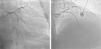

Case reportA 60-year-old-man with hypertension and type 2 diabetes as coronary risk factors was admitted to our hospital due to unstable angina. He had suffered a non-Q-wave myocardial infarction in 2006, when percutaneous coronary intervention (PCI) was successfully performed on the mid segment of the left anterior descending (LAD) and second obtuse marginal arteries. A coronary angiogram after the recent event showed a significant calcified lesion in the LM and ostial LAD without evidence of restenosis in the previous stents (Figures 1 and 2). The patient had severe left ventricular dysfunction, with 30% of ejection fraction. We planned PCI on the LM and LAD with intra-aortic balloon pump support.

The procedure was performed by radial approach using a 7F guiding catheter. Plaque preparation was performed with rotational atherectomy using a 1.5 mm burr (Figure 3) and further predilation with a cutting balloon (3-3.5 mm). After balloon dilatation, rupture of severely calcified plaque was detected by IVUS (Eagle Eye; Volcano Corporation, Rancho Cordova, CA, USA), so we proceeded to implant a 3.5 mm×20 mm CRE 8 DES in the LM and LAD (Figures 4 and 5). At this point the wire was accidentally pulled back and was reintroduced into the LM and LAD. Post-dilatation was performed with a 4 mm non-compliant balloon. IVUS examination with manual pull-back at this stage revealed that the proximal part of the stent in the LM had been crushed as a result of lateral reintroduction of the wire through a proximal stent strut. The patient remained stable with normal flow in the LM and LAD. Guided by IVUS, a second wire (Sion, Asahi Intecc, Japan), with a 30° bend in its 1 mm distal tip, was introduced within the crushed stent segment (Figure 6). Once the guidewire was positioned inside the stent, progressive dilations with small (1.5 mm) to large (4 mm) balloons were performed until the stent regained its cylindrical shape (Figure 7). IVUS exploration detected an image suggesting dissection in the proximal end of the stent (Figure 8), and so a second DES (4 mm×8 mm Onyx) was implanted in the ostial-proximal segment of the LM, overlapping the previous stent (Figure 9), with an adequate angiographic final result (Figures 10 and 11). IVUS revealed correct stent expansion and apposition in the LM (Figure 12).